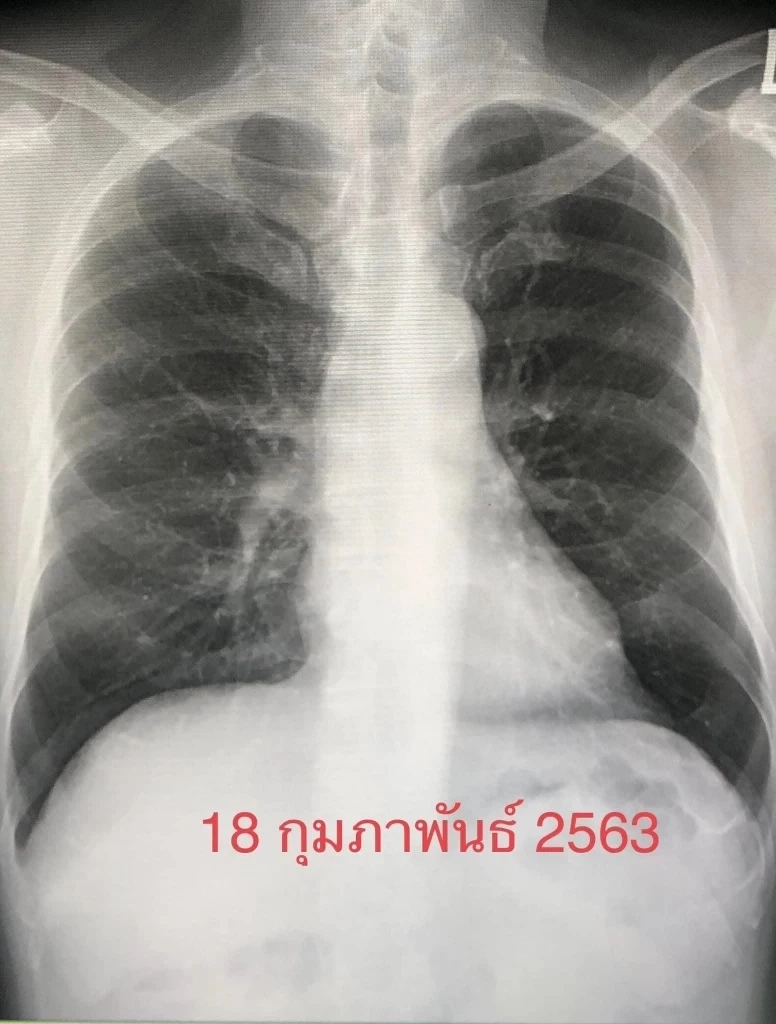

ตรวจร่างกาย ผอมลง เอกซเรย์ปอดมีฝ้าขาวทั้ง 2 ข้าง (ดูรูป) เอกซเรย์ปอดครั้งก่อนวันที่ 18 กุมภาพันธ์ 2563 ปกติ (ดูรูป) ทำคอมพิวเตอร์ปอดเห็นฝ้าขาวทั้งปอดซ้ายและปอดขวา (ดูรูป) ค่ามะเร็ง CEA ในเลือดสูง 7.4 เจาะชิ้นเนื้อจากปอดด้านซ้าย ส่งตรวจไม่พบเชื้อวัณโรค ไม่พบเชื้อรา ตรวจทางพยาธิวิทยา พบเป็นมะเร็งปอดชนิด adenocarcinoma